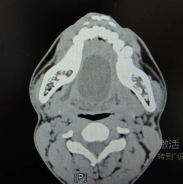

近日,我院口腔科收治一名年輕患者,因“發(fā)現(xiàn)口底及下頜下無(wú)痛性腫物一周”入院。患者近來(lái)感覺咀嚼吞咽不適,經(jīng)檢查,發(fā)現(xiàn)患者整個(gè)頜下膨隆,表面皮膚色澤正常,皮溫不高,觸診似“面團(tuán)樣”感覺,無(wú)壓痛,周界清,活動(dòng)度一般,口內(nèi)見全口底隆起,舌體被抬高,呈重舌樣改變,兩側(cè)舌下肉阜模糊不清,各唾液腺導(dǎo)管口分泌物清亮。整個(gè)腫物似橢球狀,觸診大小約6*5.5*4cm,結(jié)合面顱CT檢查擬診斷為“口底皮樣囊腫”,該腫物巨大,占據(jù)整個(gè)口底,周圍解剖結(jié)構(gòu)被推擠變形移位,加之口底密布神經(jīng)、唾液腺導(dǎo)管、血管,稍有不慎就會(huì)損傷臨近解剖結(jié)構(gòu),導(dǎo)致如舌體感覺運(yùn)動(dòng)障礙,頜下導(dǎo)管誤扎甚至切斷可能,術(shù)后口底血腫,引起窒息可能。